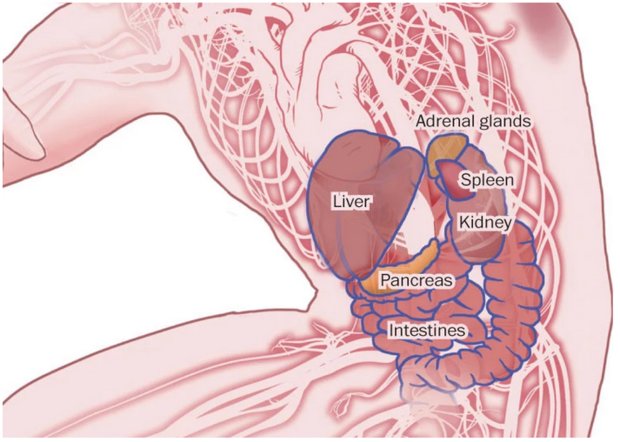

مرحله حمله

ویروس به سلول های ایمنی در جریان خون حمله می کند، و عفونت را به کبد، طحال و گره های لنفاوی انتقال می دهد. ابولا از انتشار اینترفرون، یک پروتئین ساخته شده توسط سلول های ایمنی برای مبارزه با ویروس، جلوگیری می کند.

سلول های ایمنی آلوده از طریق جریان خون یا مجراهای لنفی به دیگر بافت ها و اندام ها، به خارج از طحال و گره های لنفاوی، انتقال می یابند.

اختلالات چند سیستمی

• ابولا یا توسط سلول های آلوده به ویروس یا با پاسخ التهابی شدید بدن، به بسیاری از بافت ها آسیب می رساند.

• اختلال غدد آدرنال، منجر به فشار خون پایین خطرناک و کاهش توانایی تولید هورمون های استروئیدی می شود.

• به بافت های همبند بدن، که نقش سلول های پوشاننده برای حفره ها و سطوح بدن را دارند، حمله می شود.

• نارسایی کبد و کلیه رخ می دهد.

• پانکراس آلوده می تواند منجر به درد شدید شکم شود.

• آسیب روده باعث اسهال و کاهش آب بدن می شود.

مایع در مغز تجمع می یابد. تشنج باعث گسترش خون عفونی و سایر مایعات بدن بیمار می شود.